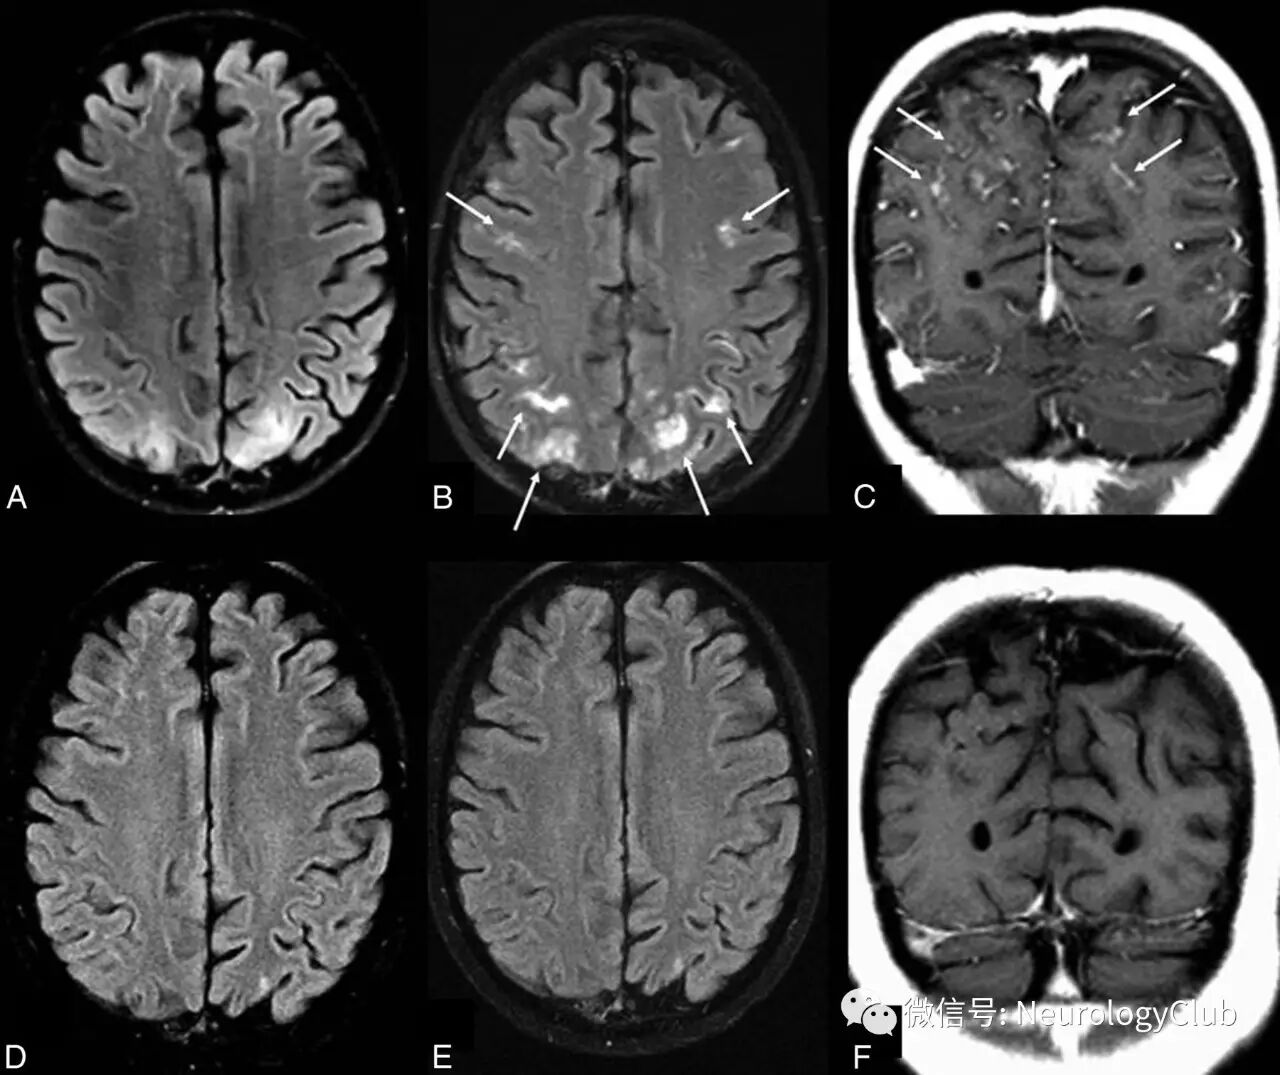

颅脑影像学有助于诊断PRES以及鉴别诊断。血管源性水肿可以通过CT来发现,但颅脑MRI更敏感。由于缺乏诊断金标准,无法评估MRI的特异性。颅脑MRI典型表现为双侧顶枕叶为主的血管源性水肿,呈T1低信号,T2/FLAIR高信号,DWI等或低信号,ADC高信号。通常累及皮质下白质,较少累及皮质。水肿几乎累及双侧,不完全对称。

(图2:典型的黑水像PRES影像学表现)

影像学表现可分为四型:顶枕型,全脑分水岭型,额上回型和中央变异型。影像学分型和水肿严重程度都不与临床表现分型和严重程度相关。额叶和颞叶受累者约占75%。累及基底节和脑干者有1/3,累及小脑者约占半数。这些部位的水肿一般是伴随着顶枕部位的受累。病变不累及顶枕区域者少见。仅累及单侧大脑和孤立性脑干与小脑水肿者需要排除其它疾病。

(图3:均为黑水像;A-C:顶枕型PRES;D-F:全脑分水岭型PRES;G-I:额上回型PRES)